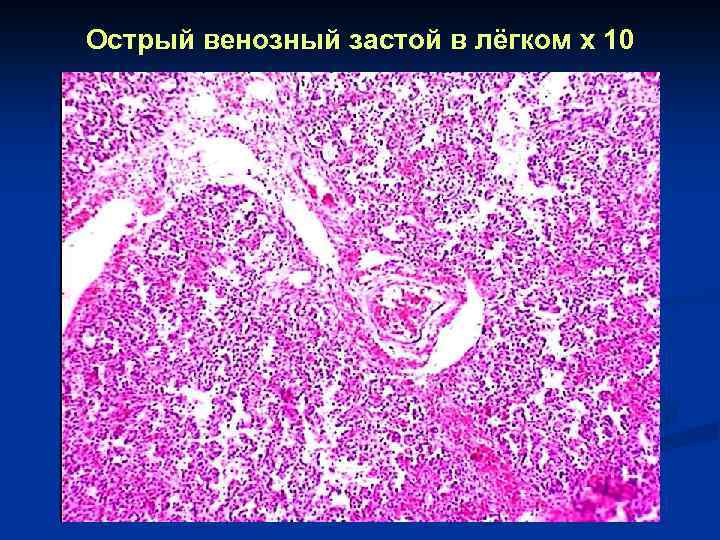

Острый венозный застой в лёгком x 10

Острый венозный застой в лёгком x 10